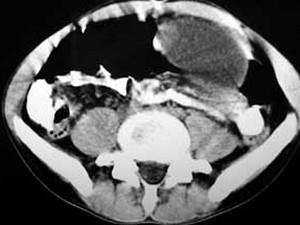

问题 男,33岁,腹部外伤后两月余,腹部疼痛,行CT扫描所见如图,最可能的诊断是 ( )

选项 A、畸胎瘤 B、腹腔包裹性积血 C、慢性胰腺炎 D、胰腺创伤性假性囊肿 E、急性胰腺炎

答案 D